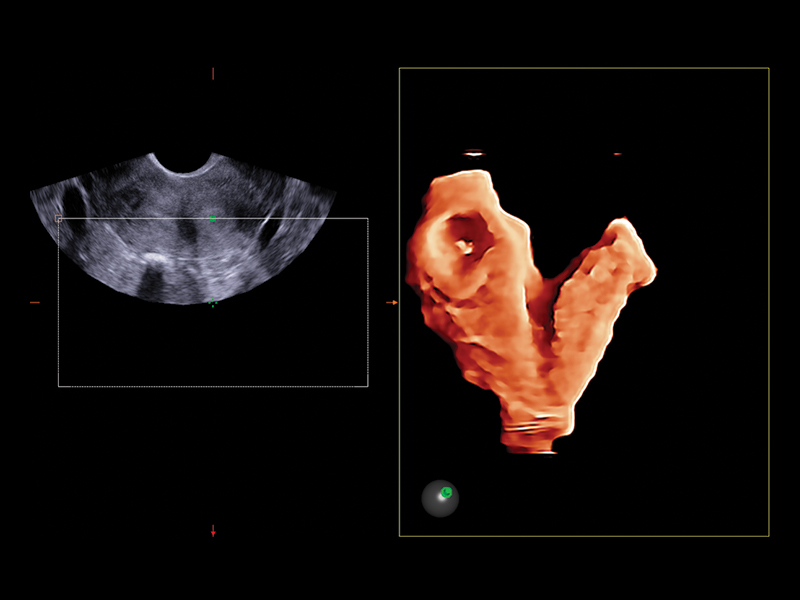

A standard examination very frequently highlights situations that need to be analyzed in greater detail. Esaote’s new volume rendering algorithm offers realistic three-dimensional reconstructions of the internal cavity of the uterus, within a few seconds, for evaluation of uterine shape and size. Thick Slice Imaging (TSI) 3D environment is particularly useful when the purpose is to highlight a well-defined and confined structure, such as the endometrium, allowing for a completely customizable concavity line.